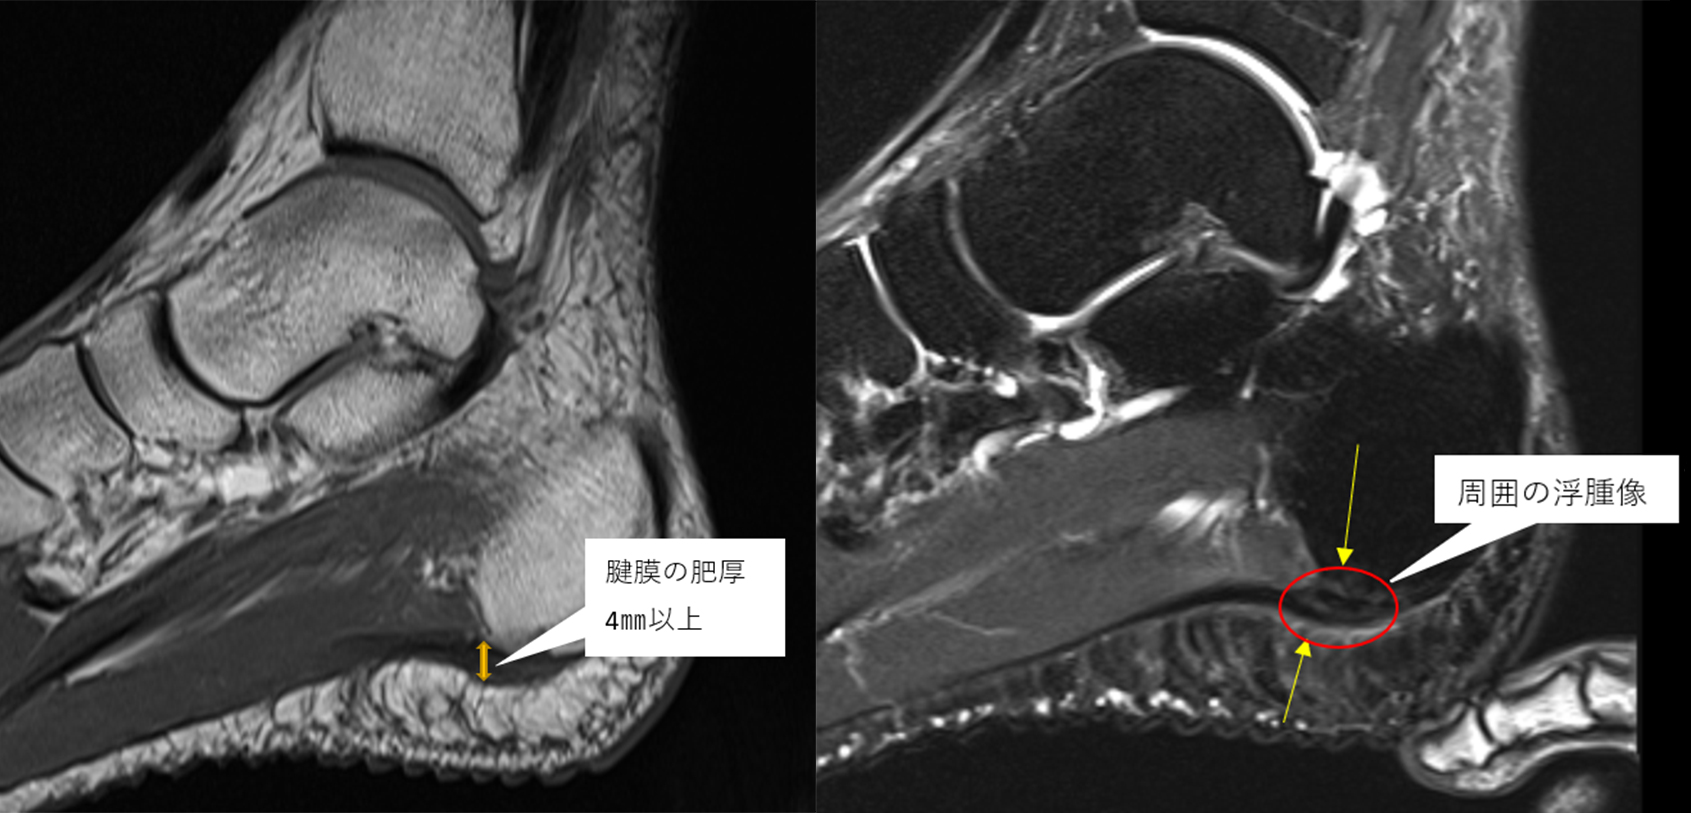

MRI検査

超音波では捉えにくい深部の変性・部分断裂・骨髄浮腫まで詳細に確認できます。

特に「レントゲンで異常なし」と言われても痛みが続く場合、MRIで初めて腱膜の変性や断裂が確認されるケースは少なくありません。

また踵骨疲労骨折・神経の圧迫・腫瘍など他疾患との鑑別にも不可欠です。